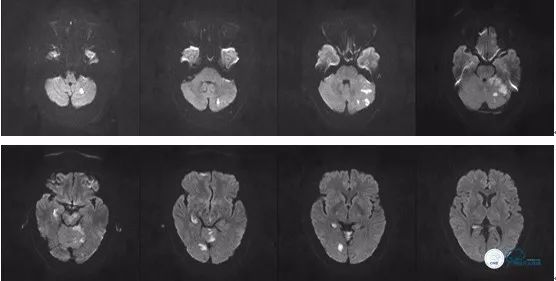

术后头颅MR DWI序列:

图14

图15